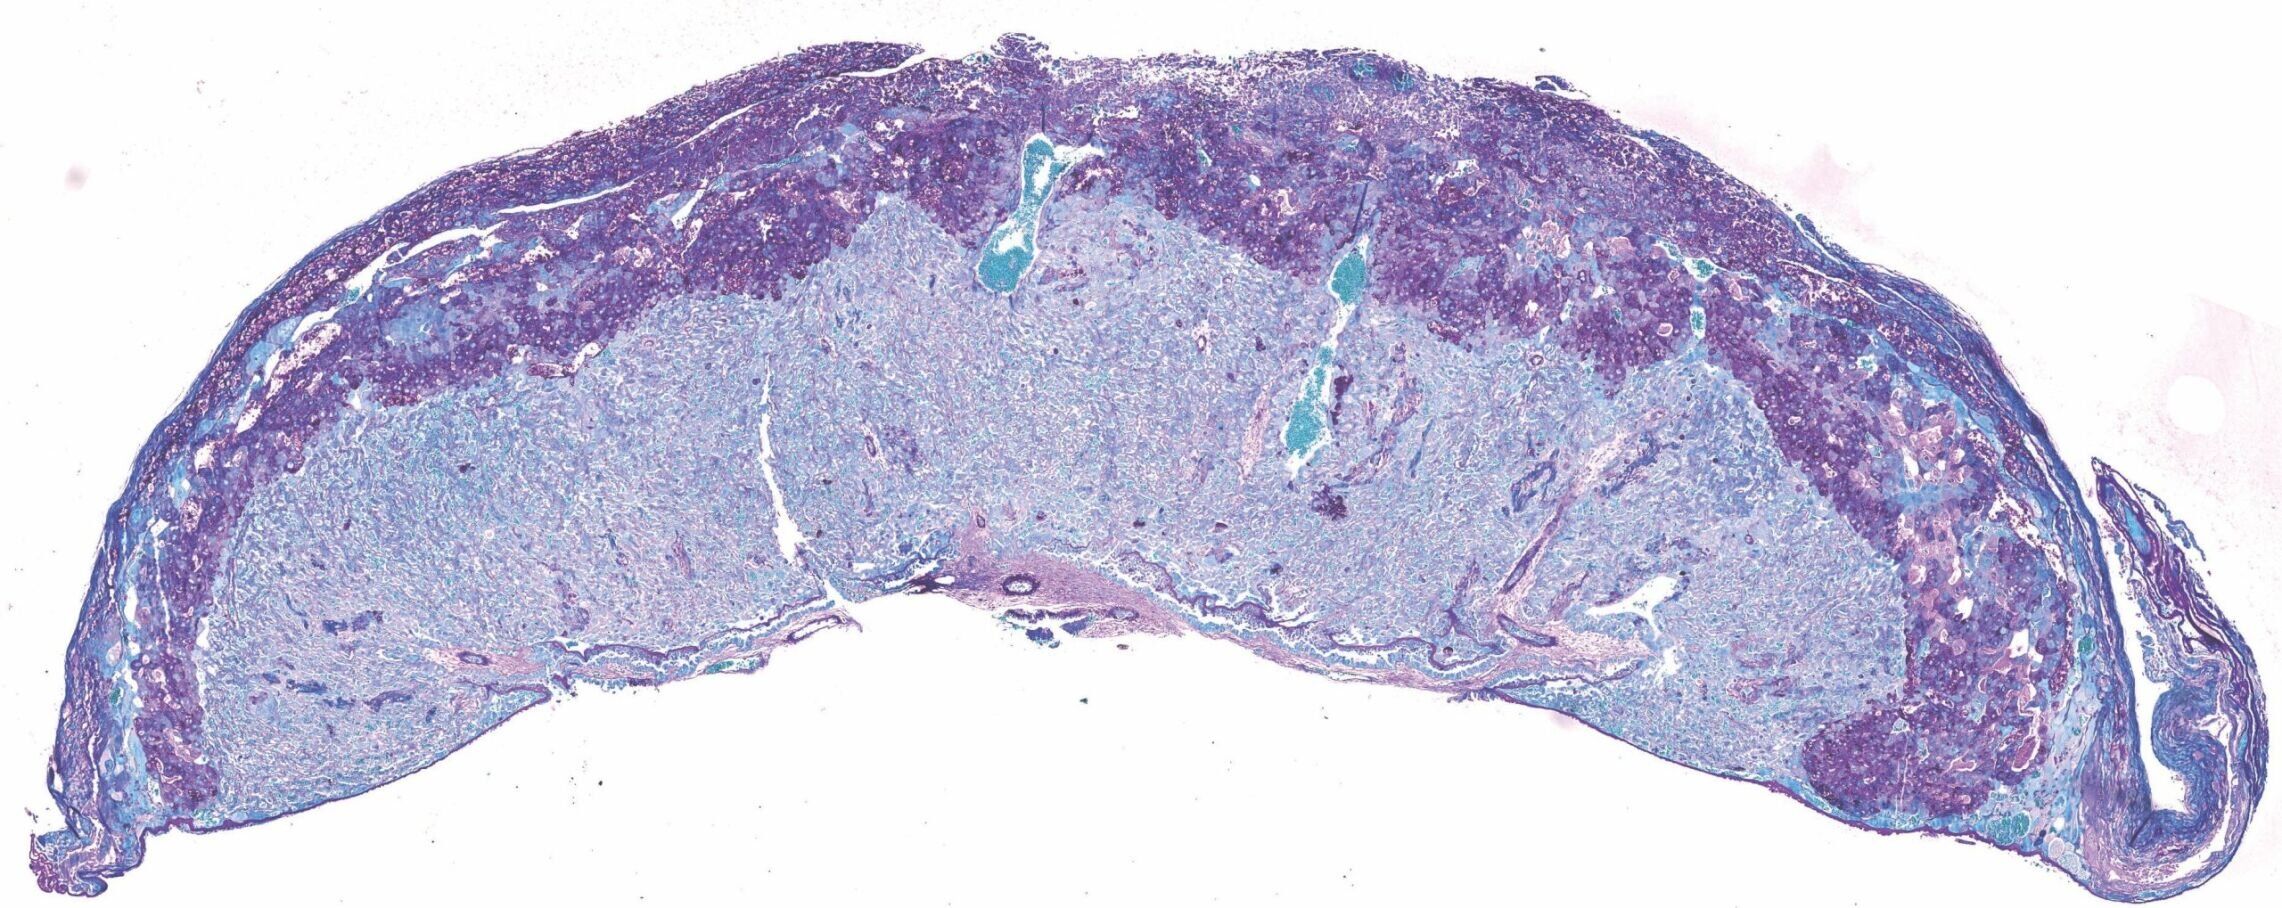

University of Cambridge scientists have discovered that the good gut bacteria Bifidobacterium breve in pregnant mothers regulates the placenta's production of hormones critical for a healthy pregnancy. (Jorge Lopez-Tello/ Cambridge University via SWNS)

Over 150 biological processes in the placenta - involving over 400 different proteins - were found to be different in mice with, and without, Bifidobacterium breve in their gut. (Jorge Lopez-Tello/ Cambridge University via SWNS)

In the study, more than 150 biological processes in the placenta - involving over 400 different proteins - were found to be different in mice with, and without, Bifidobacterium breve in their gut.

The placentas of mice with Bifidobacterium breve in their gut also produced more of the hormones important for pregnancy, such as prolactins and pregnancy-specific glycoproteins.